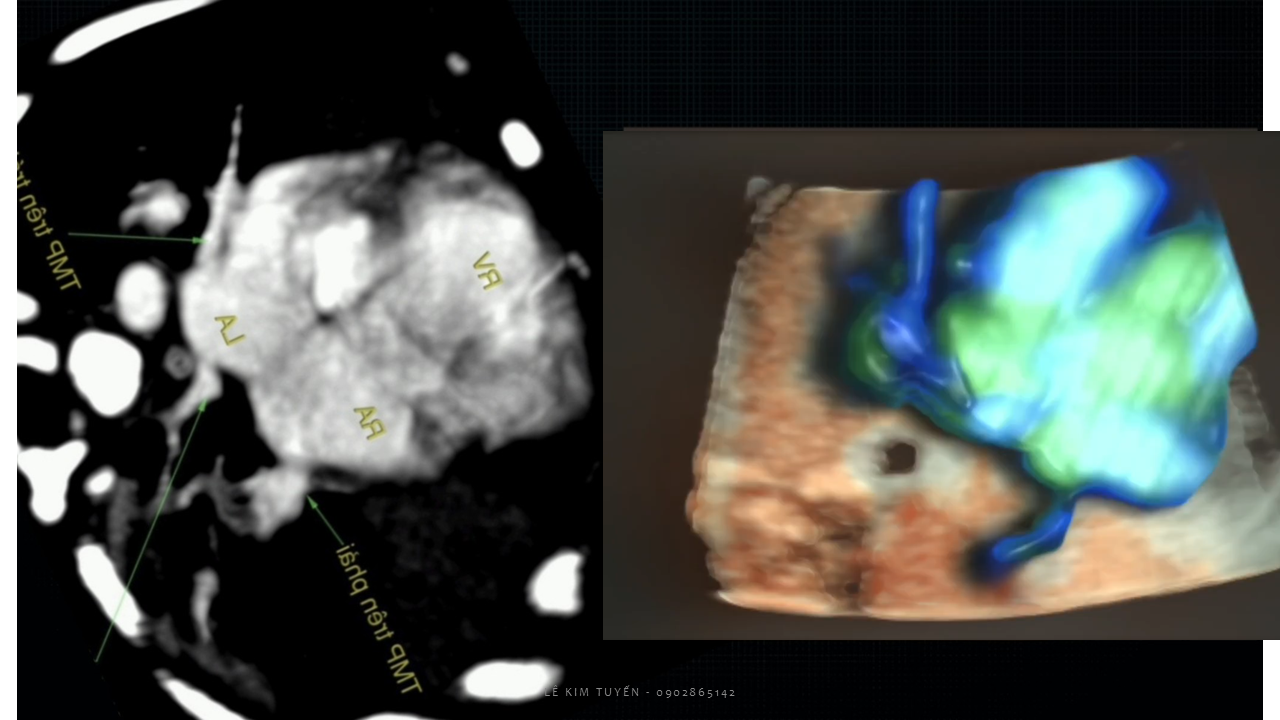

Siêu âm tim thai - Các kỹ thuật hiện đại

TS. BS. Lê Kim Tuyến

Bệnh viện Tim Tâm Đức